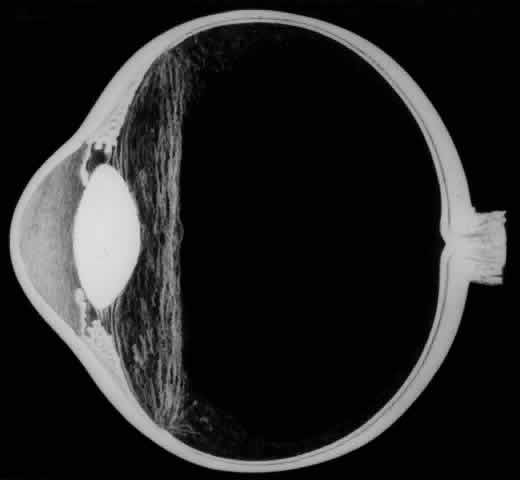

The earliest biomicroscopic changes preceding the development of a giant retinal tear were syneresis and liquefaction of the vitreous gel, converting the posterior and central portions of the vitreous body into a large lacuna (Fig. 14). Later, the anterior gel became condensed, and its posterior aspect formed an equatorially oriented membrane extending across the vitreous cavity (Fig. 15). This membrane did not oscillate with ocular movements, suggesting that it was under tension. Marked contraction of this membrane seems responsible for tearing the retina along the posterior border of the vitreous base (Fig. 16). Liquefied vitreous gel facilitated inversion of the posterior retinal flap (Fig. 17).

Fig. 16. Contraction of this equatorially oriented membrane extending across the vitreous cavity produces a giant tear along the posterior border of the vitreous base.

Fig. 17. After the formation of a giant retinal tear, the posterior retinal flap inverts into the liquefied vitreous (arrow).